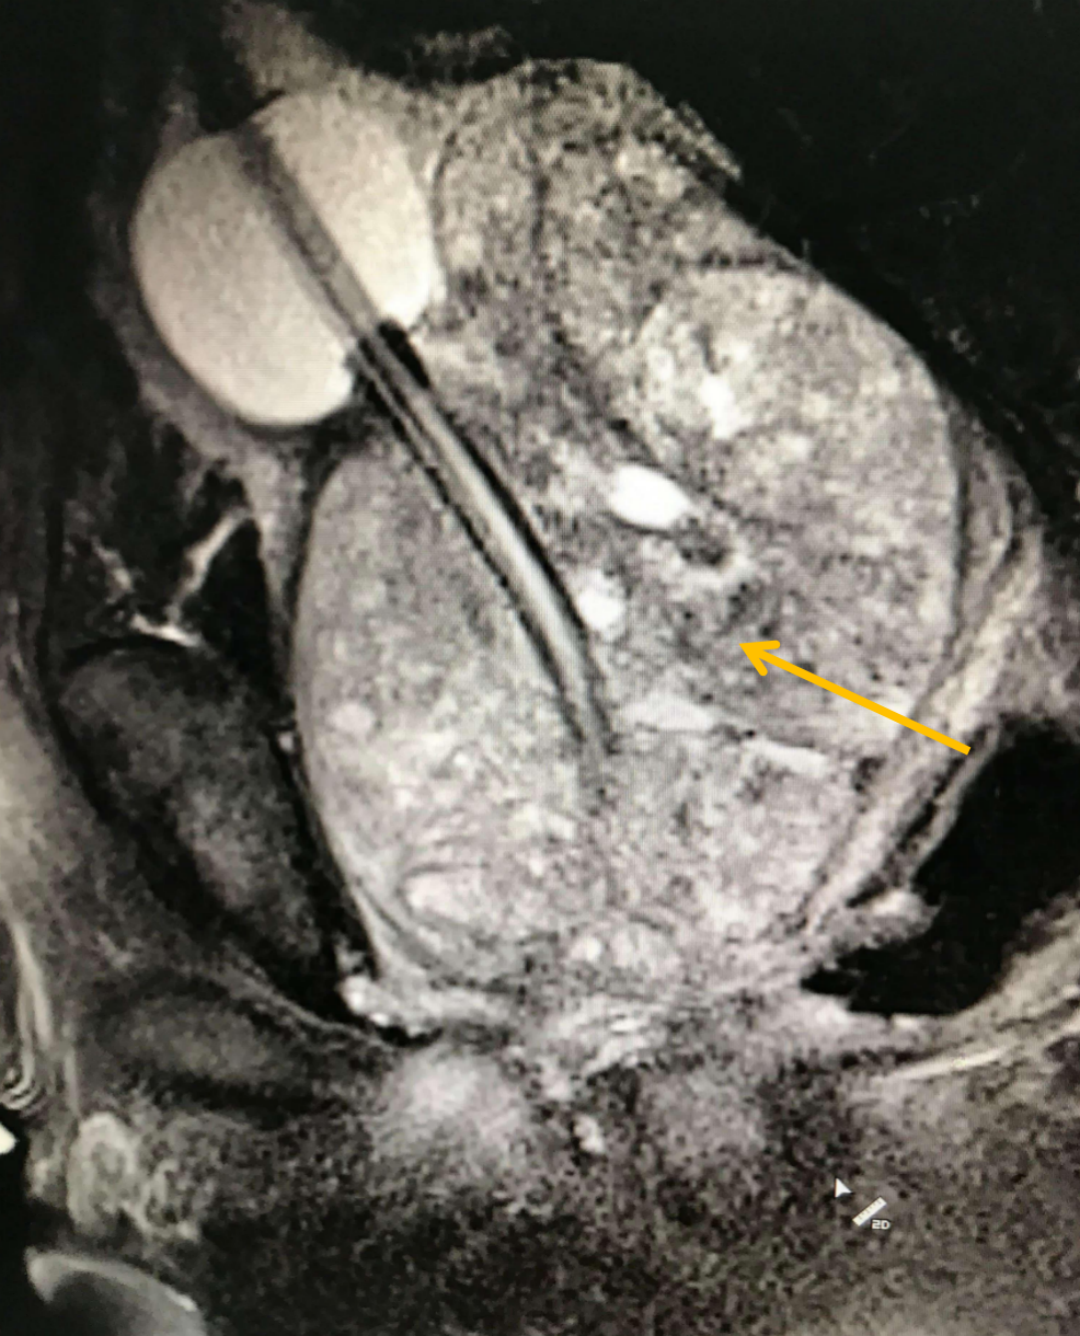

下面这张影像,展示的是一位重度前列腺增生患者的腺体——它如同一个巨大的核桃,紧紧扼住了尿道的“咽喉”。看到这样的影像,我们对于他能否恢复顺畅排尿,还能抱有多少期待?

图:增生的前列腺(箭头所指)挤压尿道,导致排尿困难